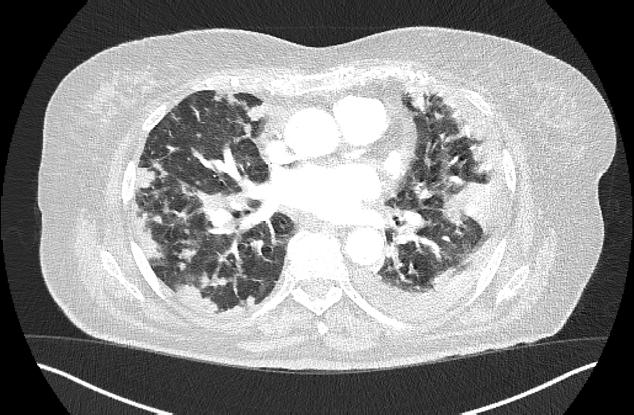

Initial thoracic CT scan (lung window). Multiple bilateral opacities and left pleural effusion.

A 78-year-old female, non-smoker, with no occupational or habitual exposure to respiratory toxins, presented to the emergency department with acute respiratory failure, reporting dry cough, exertional dyspnoea at minimal effort and anorexia – symptoms which had begun about 1 week prior. The patient received antibiotic therapy per the general practitioner’s recommendation (a second-generation cephalosporin for 7 days), but the symptoms persisted. Chest computed tomography (CT) revealed multiple nodular and micronodular hyperdensities diffusely distributed in both lung fields, some with a tendency to confluence, as well as left pleural effusion – an aspect suggestive of bronchopneumonia (Figure 1). Laboratory tests revealed leukocytosis, neutrophilia, a significant inflammatory syndrome, and mild normocytic normochromic anaemia.